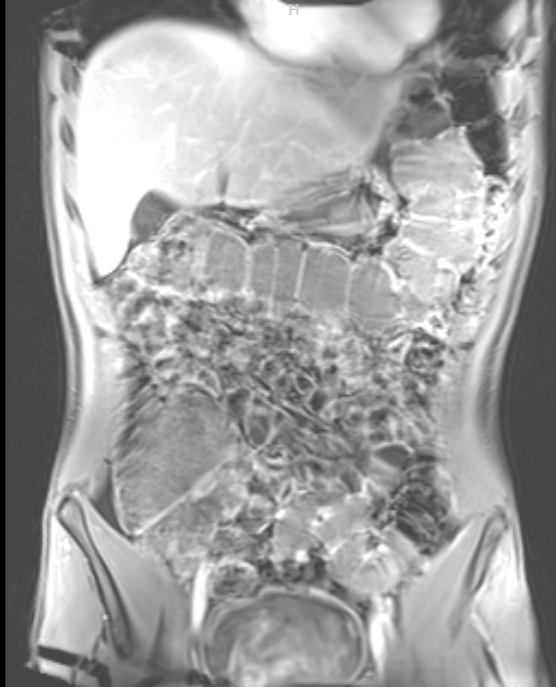

ЗАПОР 3 ГОДА Аноним 28/10/25 Втр 17:42:54 1646669 Ответ

image.png 303Кб, 556x687

image.png 250Кб, 572x698

Сап всем, у меня проблема с запорами не проходят 3 года. Мне 22 года, я обходил многих врачей. Сделал гастро и эндоскопию и ничего не выявили. Сделал мрт живота(прикрыл), и единственное что у меня выявили это "Удлинённая сигмовидная кишка(sigma elongatum)". Это возможно и причина проблемы. Проблем кроме запоров нет, я регулярно занимаюсь физическими активностями, нормальная диета и выпиваю по 2 литра воды в день.

Можете мне помочь с этой проблемой, мнение по этому вопросу от тех кто сталкивался с таким же или специалистов. Буду благодарен.